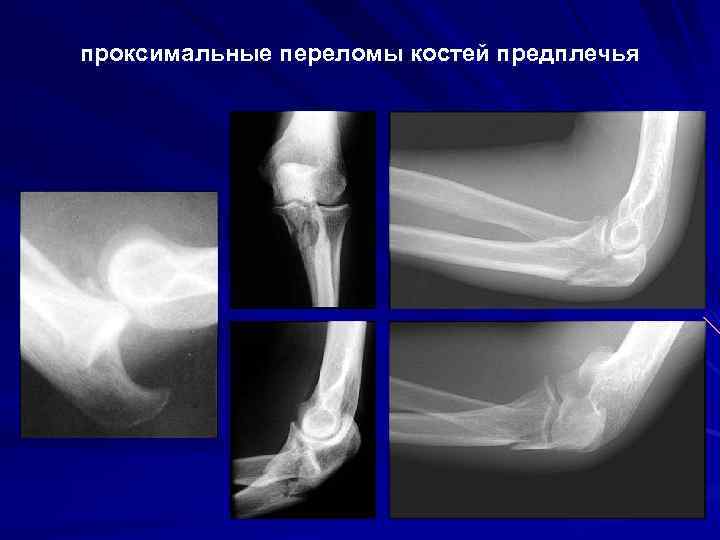

проксимальные переломы костей предплечья